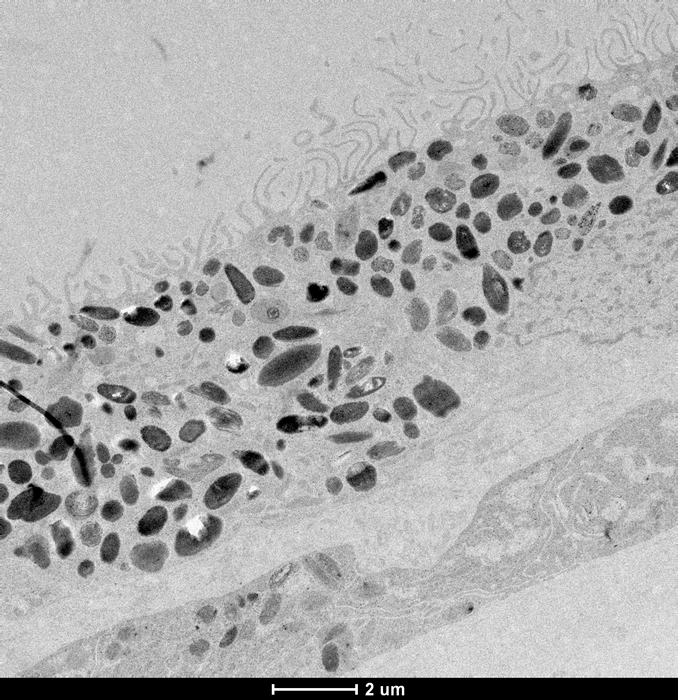

The researchers took skin samples from 79 participants with and without the late stage of AMD, called geographic atrophy. Their skin cells were reprogrammed to revert to stem cells called induced pluripotent stem cells, and then guided with molecular signals to become retinal pigment epithelium cells, which are the cells affected in AMD.

Retinal pigment epithelium cells line the back of the retina and are essential to the health and functioning of the retina. Their degeneration is associated with the death of photoreceptors, which are light-sensing neurons in the retina that transmit visual signals to the brain and are responsible for the loss of vision in AMD.

Analysis of 127,600 cells revealed 439 molecular signatures associated with AMD, with 43 of those being potential new gene variants. Key pathways that were identified were subsequently tested within the cells and revealed differences in the energy-making mitochondria between healthy and AMD cells, rendering mitochondrial proteins as potential targets to prevent or alter the course of AMD.